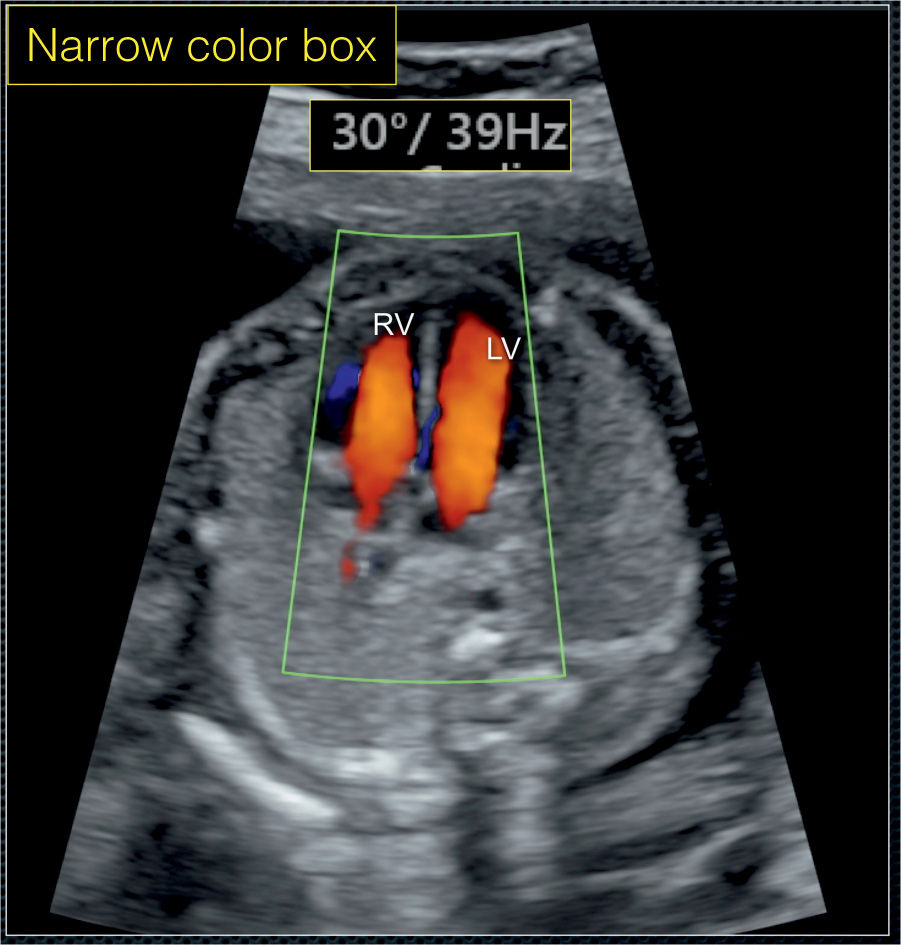

The sections of this tube will go on to form all the structures of the future heart. Embryonic heart pulsation is the earliest proof that the embryo is alive. A fetal heartbeat can be seen and heard during prenatal ultrasound by the sixth week of gestation. Right now the doctor is telling that i am having a. Color Doppler in Fetal Echocardiography Obgyn Key.

Hi, i currently in 8 weeks. A slow fetal heart rate is termed fetal bradycardia and is usually defined as 1: Ctg recordings were reassuring or nonreassuring (namely variable or persisting late. Two heart tubes have formed in the embryo. Color Doppler in Fetal Echocardiography Obgyn Key.